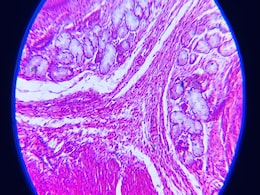

Scientists Reportedly Reversed Type 1 Diabetes by Reprogramming Patient's Fat Cells into Insulin-Producing Cells

Chinese researchers have, for the first time, reprogrammed a woman’s fat cells to become insulin-producing pancreatic cells, reversing her need for insulin injections for over a year. In this study, fat cells were chemically reverted into stem-like cells and transformed into islet cells, which are normally found in the pancreas. The cells, implan...